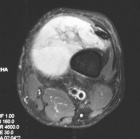

62 year old male with left thigh swelling, soft tissue mass x several years.

Complains of size of the mass, but does not have pain in left thigh.+

Zoom image: Cell stain Cell stain.